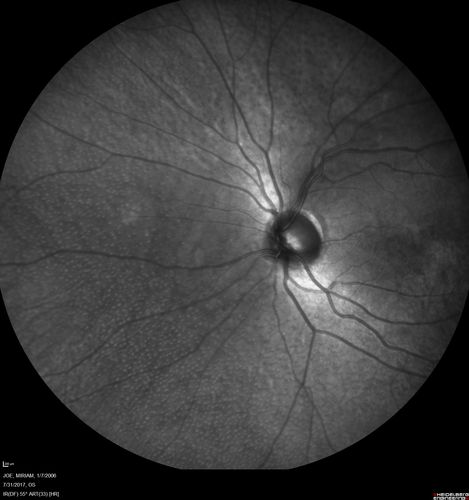

Fundus Albipunctatus

12 year old female with normal vision. She has 4 siblings all of whom have either white spots or spots on IR. Genetic testing by parents was deferred.

Retinitis Punctata Albescens - Fundus Albipunctatus